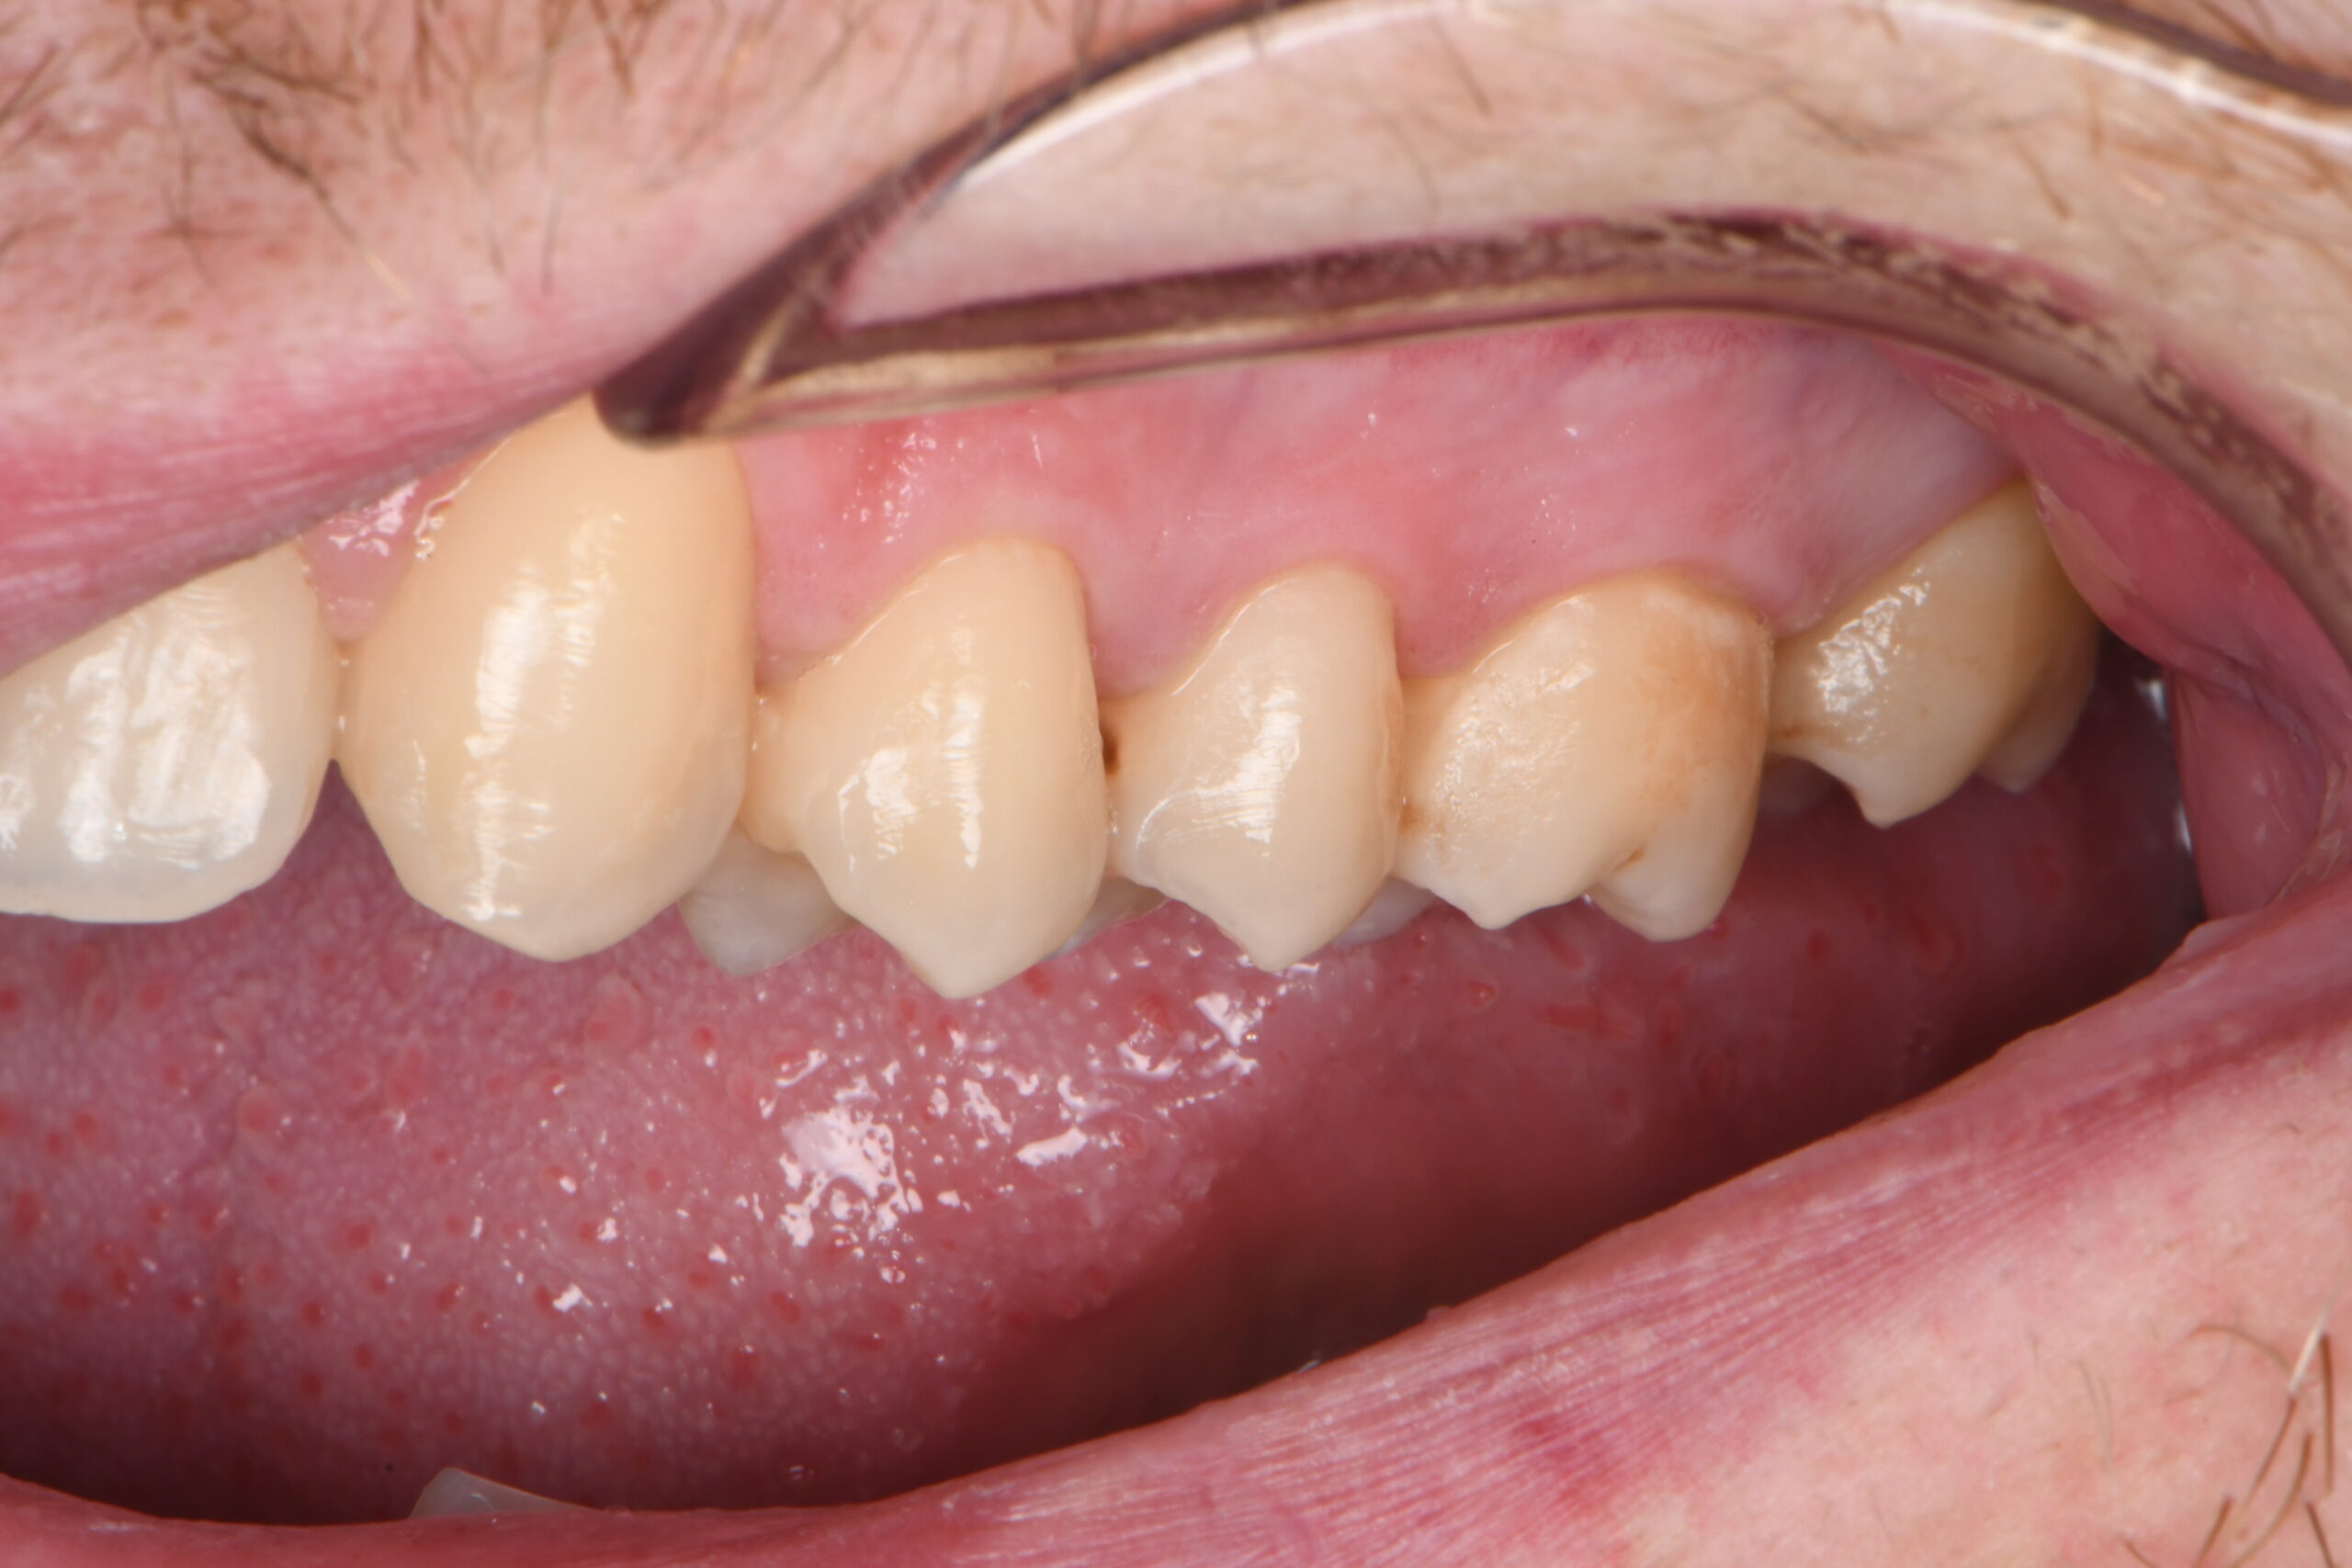

Lower row of molars and premolars with visible gums and inner cheek.

Pre-op vestibular view.